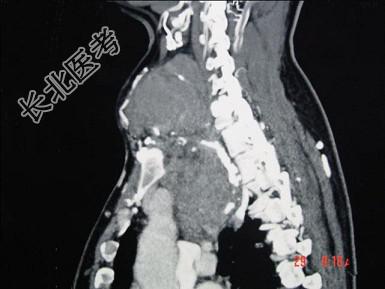

- 多项选择题女,48岁, 颈部包块3年,近来胸闷、憋气、胸痛, CT扫描如图,正确的描述或诊断是 ( )

A、胸骨后甲状腺肿

C、双侧甲状腺肿大

D、胸骨后甲状腺肿是指甲状腺50%位于胸骨后

E、胸骨后甲状腺肿是指甲状腺60%位于胸骨后